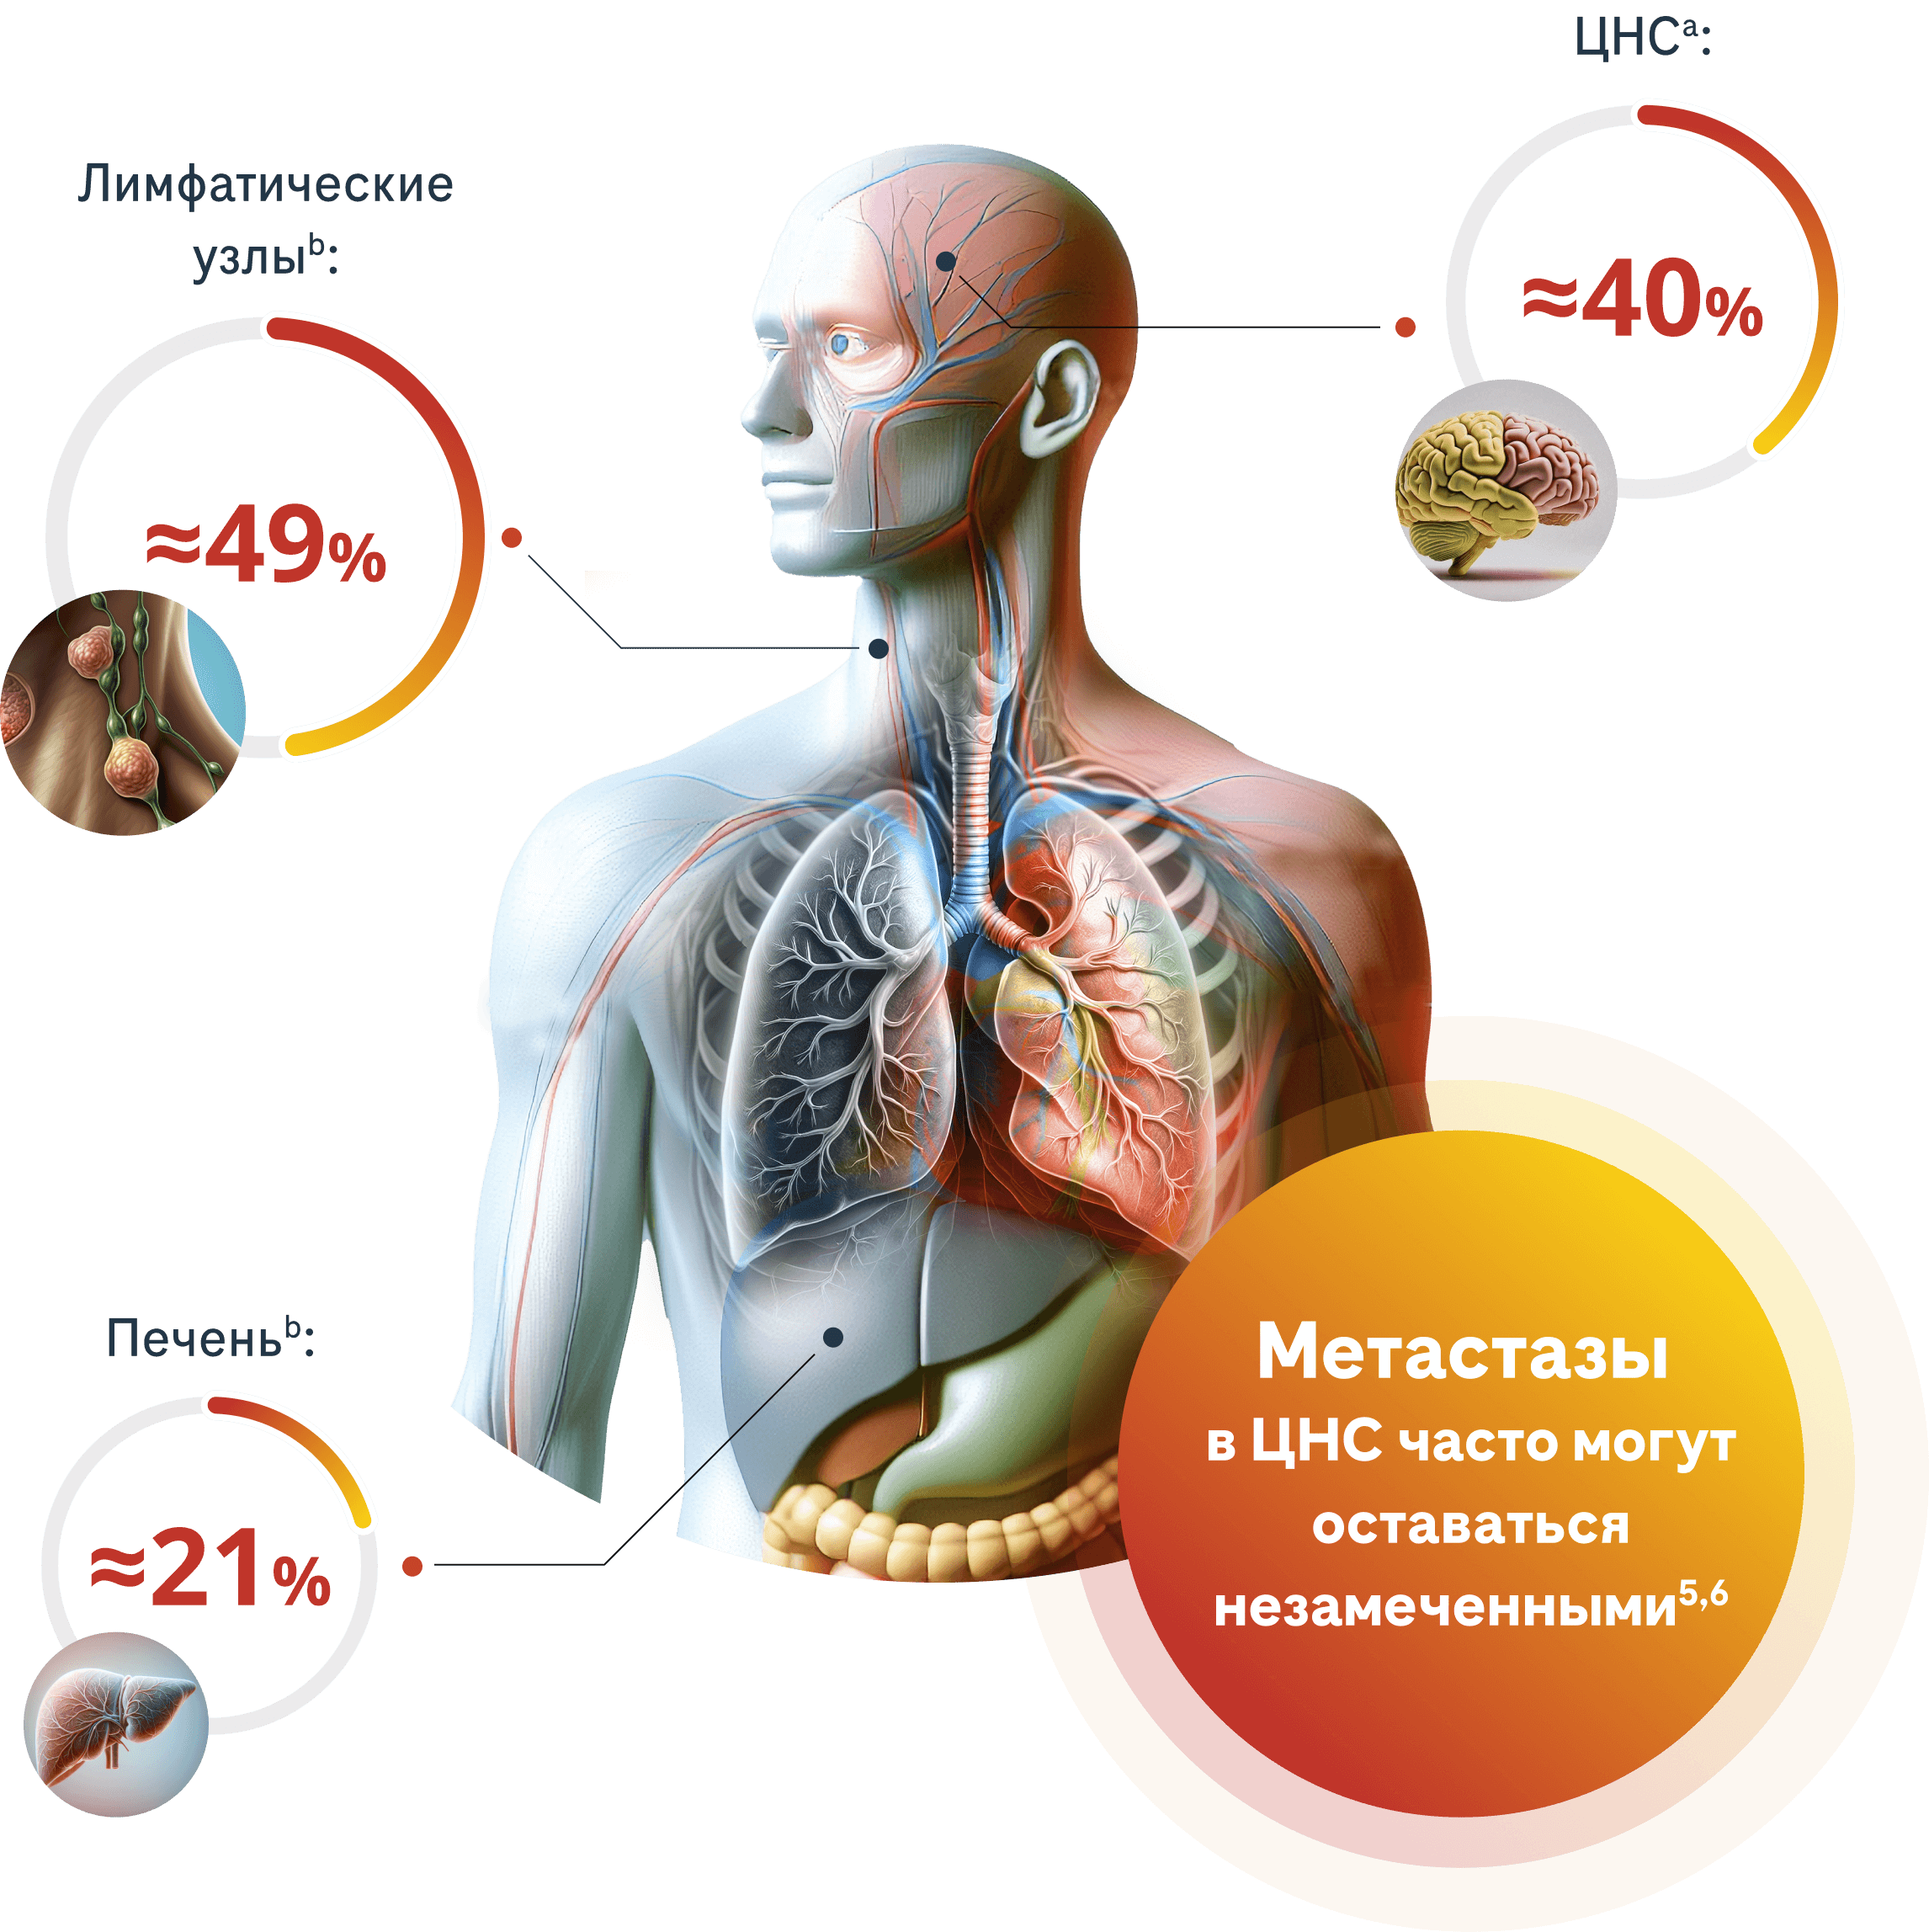

ALK-положительный метастатический немелкоклеточный рак лёгкого (мНМРЛ) может привести к прогрессированию заболевания, включая поражение центральной нервной системы (ЦНС)3,4

Наиболее частое расположение экстраторакальных метастазов у пациентов с впервые диагностированным мНМРЛ в исследовании ALEX3

a Идентифицировано независимым наблюдательным комитетом (IRC).

b Идентифицировано исследователем.

Это анализ характеристик пациентов в клиническом исследовании Алектиниба, который может не быть репрезентативным для всей популяции пациентов с ALK+ мНМРЛ.

В ретроспективном анализе практически у половины пациентов с НМРЛ и метастазами в ЦНС не было симптомов7

≈50%

Бессимптомные метастазы в ЦНС (N=62)

Микрометастазы

могут пересекать

гематоэнцефалический

барьер и могут перерасти

в более крупные

поражения5,6